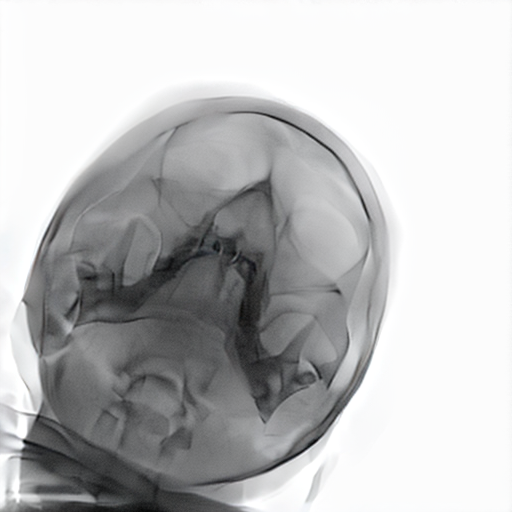

Refer to caption

Figure 3: Trade-off between structural fidelity (SSIM) and realism (CFID) for the evaluated models.

As shown in Table 3, CycleGAN-Turbo achieves the strongest performance on distributional metrics such as CFID and density, but this comes at the cost of anatomical fidelity. The implementation of the structural similarity loss did not yield the expected outcomes. The qualitative results in Table 2 reveal that it introduces spurious features, especially in the second row, undermining structural correctness. In contrast, Hierarchy Flow preserves anatomical details exceptionally well by applying minimal transformation, resulting in outputs that closely resemble the input and thus offer limited to no domain adaptation. As noted in Figure 3 and Table 3, the model completely breaks down at high style strengths values without improvement in FID.

MedShift is evaluated in three τ\tau settings to explore the trade-off between structural preservation and generative realism. At τ=0.6\tau=0.6, the model is second only to HierarchyFlow in maintaining structure, while significantly outperforming it in CFID and coverage. The low-fidelity setting (τ=0.3\tau=0.3) reaches CFID values comparable to CycleGAN but with far fewer anatomical distortions. The intermediate configuration (τ=0.45\tau=0.45) provides a good trade-off, as seen in Table 2. Z-STAR maintains structure but fails to transfer style effectively to the lower jaw, while SDEdit captures pixel intensities well but introduces artifacts into the cranial region, particularly in the second example. As shown in Figure 3, MedShift achieves a more favorable balance between structural fidelity and image realism across all τ\tau settings, outperforming the other models in this trade-off space. This reinforces the findings based on average ranking, confirming MedShift as the most well-rounded strategy.